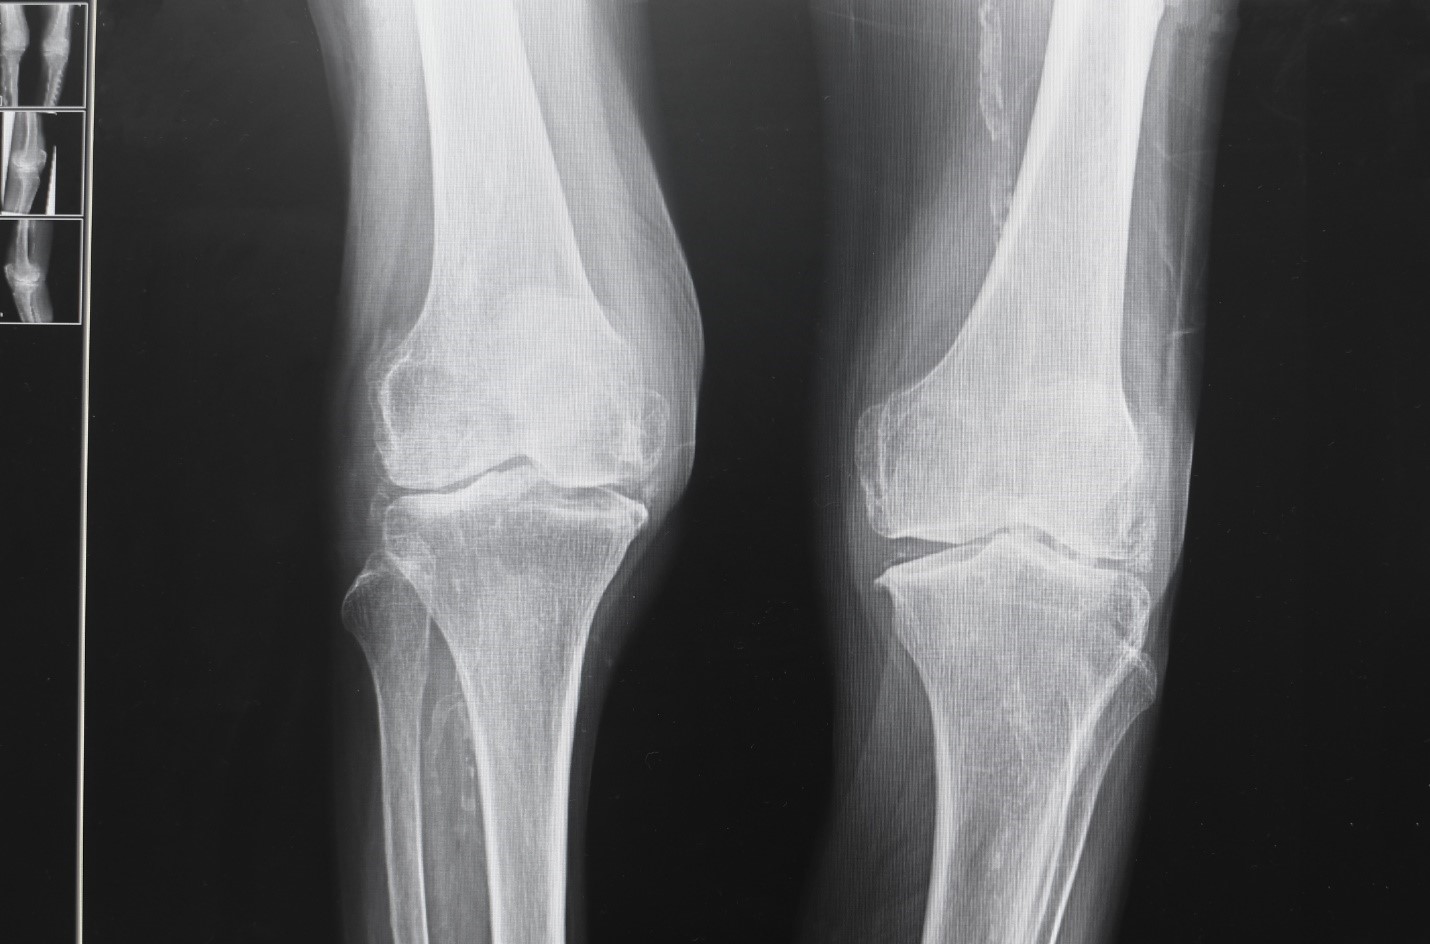

Our most successful knee pain treatment programs include: